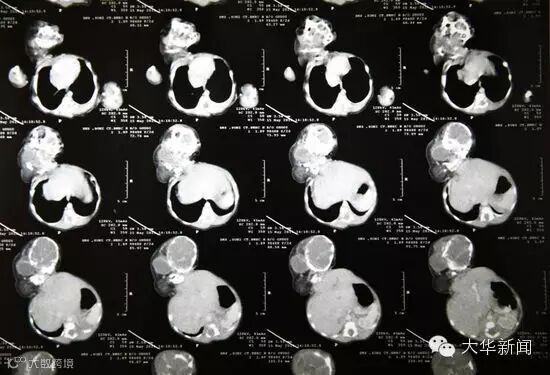

据报道,这名女子叫阿穆雷克·拜尔瓦(Amlekha Bairva),现年22岁。4月份时,拜尔瓦在村中政府公立小医院中生下一名怪婴。这名女婴体重约2公斤,属于寄生双胞胎。她的双胞胎姐妹已经部分成形,头部通过脖子长在其肚子上。

目前,这名女婴正在医院新生儿重症监护室中接受医疗观察,医生们希望其情况稳定后尽快帮其手术,切除多余器官。当地医生表示,手术成功的希望很大。一名医生说:“这属于寄生双胞胎,女婴身体很健康,有正常心跳,没有其他内部或外部复杂结构,这会增加她幸存的几率。”